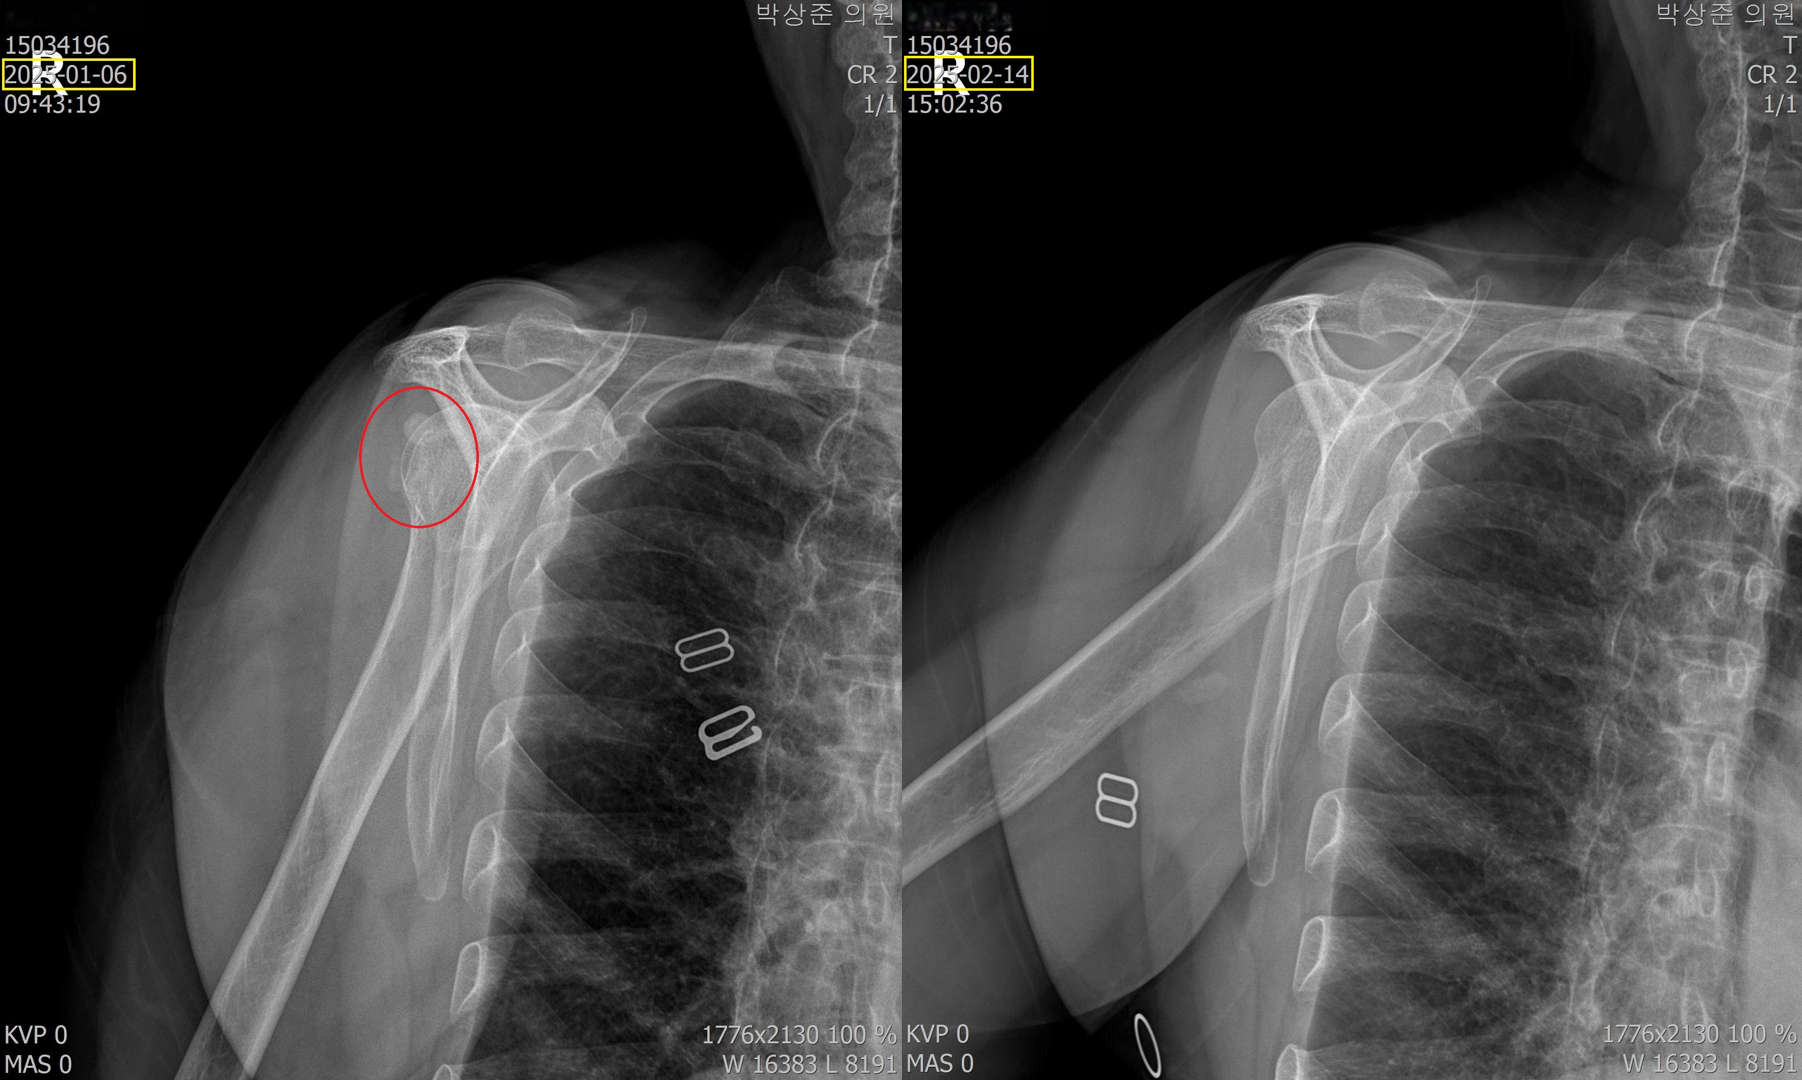

(2) 갑자기 급작스런 어깨 통증으로 방문한 환자

이분은 극심한 통증으로 아침 진료 시작시간 30분전부터 와서 기다리고 있는 분입니다. 내원 3일전부터 약간씩 아프다 내원 전날 밤에 통증이 극심해져서 밤새 잠도 못자고 병원에 오셨습니다. 통증이 워낙 심해서 옷을 입고 벗는것도 스스로 불가능했고 초음파검사기를 가져다 대는것도 아파하는 정도였습니다.

초음파 검사에서 보면 어깨에 아주 커다란 석회가 있고 주변으로 염증이 심한 상태였습니다.

처음에는 염증을 가라앉히는 주사, 먹는약, 물리치료로 통증을 가라앉히고 그 다음부터 5회의 석회흡입술과 체외충격파 치료를 했습니다.

위의 비포 & 애프터 사진을 보면 알 수 있지만 5회의 석회 흡입술과 체외충격파 치료로 아주 커다란 석회가 드라마틱하게 사라진걸 볼 수 있습니다. 이 환자분의 경우 염증 주사를 맞고 이틀만에 통증은 거의다 사라졌고 커다란 석회마저 완전히 제거되어 치료 만족도가 매우 높은 분이었습니다.